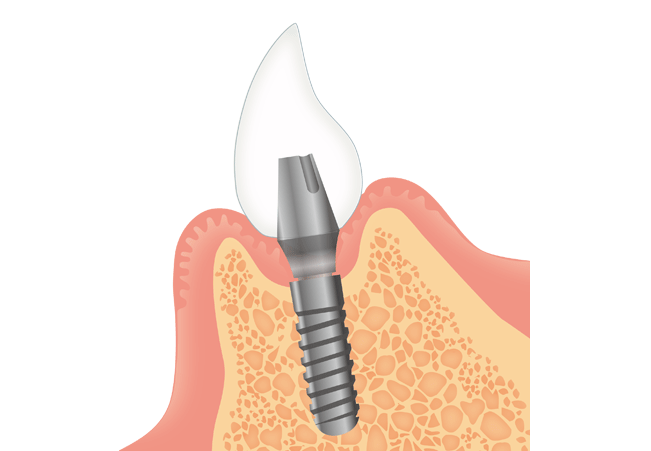

インプラント治療とは、歯を失ってしまった時に行う治療法の一つです。人工の歯根(歯の骨に植っている部分)を顎の骨に埋め込み、その上に人工的な歯(アバットメント+人工歯)を取り付ける構造になっています。その他取り外し式の入れ歯や両隣の歯を削って橋をかけるように固定するブリッジという方法もありますが全く異なる治療法となっています。

一方、インプラント治療は、歯を抜いた箇所(歯根が残っていない部分)に人工の歯根(インプラント)を埋め込み、上部構造(人工歯)を装着する治療法です。